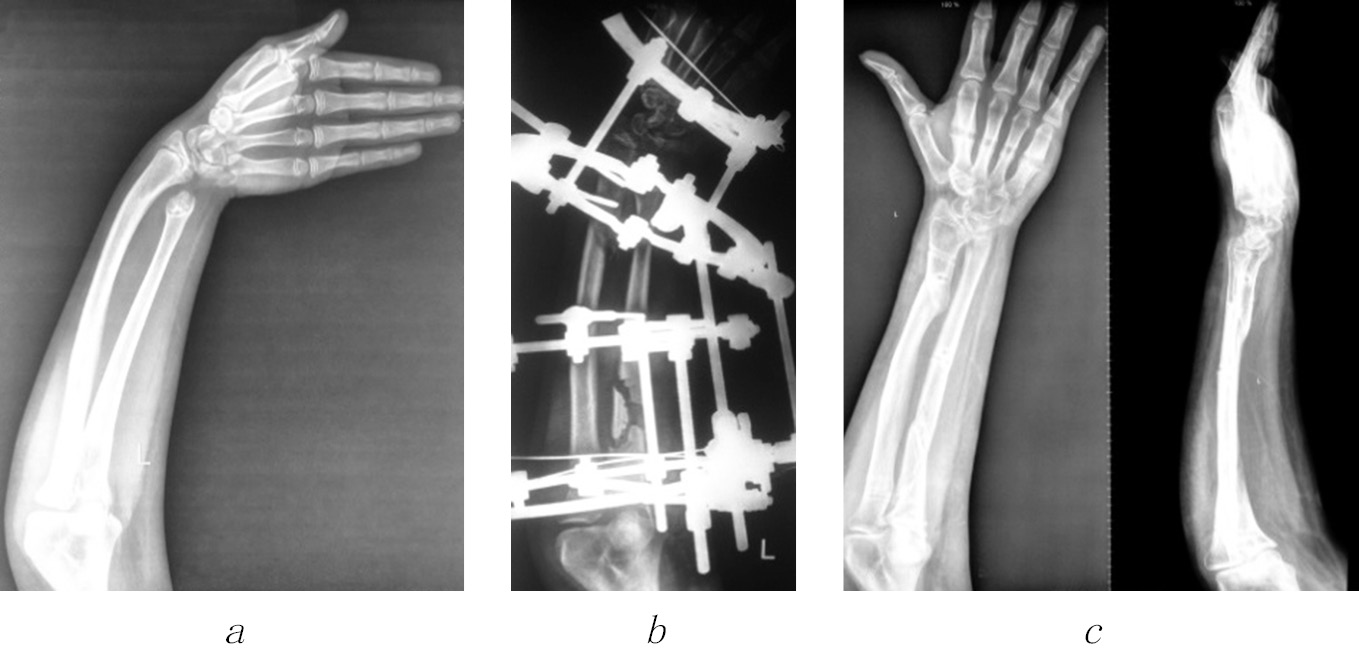

We believe that elimination of deformity of only a shortened bone is not enough, since in the process of child growth, the adjacent forearm bone is deformed, causing pronounced cosmetic and functional disorders (Fig. 5).

Fig. 5. Radiographs of the left forearm of patient G. before (a), in the process (b), and after (c) the elimination of the ulnar clubhand